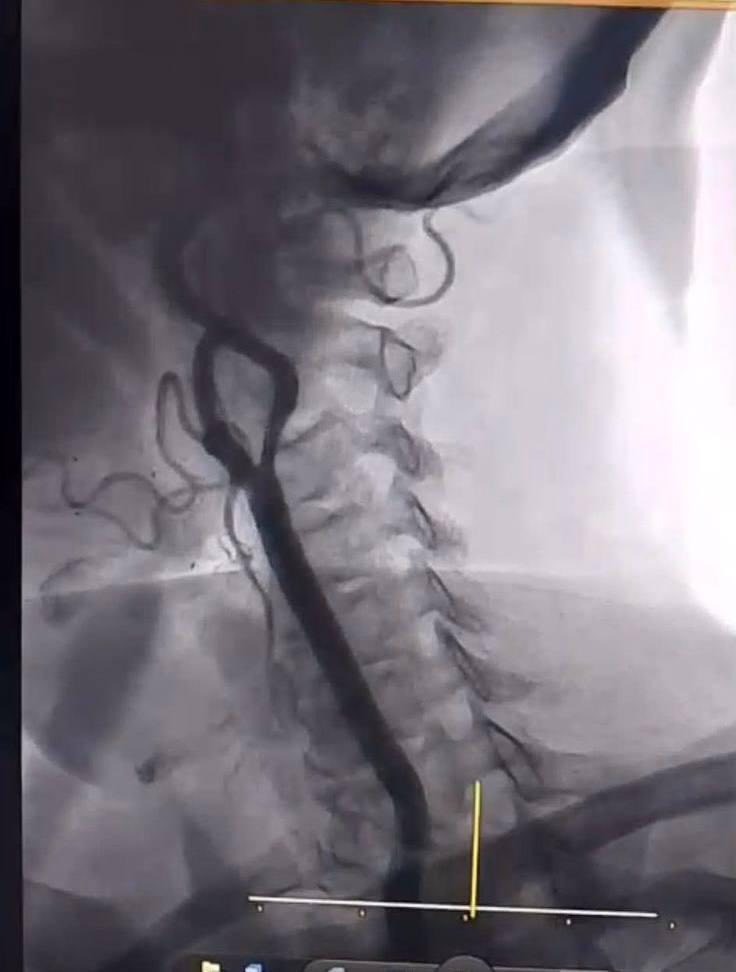

وأشار عبد الهادي إلى، أن المستشفى شهد إجراء عمليتين نوعيتين؛ حيث تمثلت العملية الأولى بـ فتح الشريان الفخذي الأيمن وزرع شبكة على يد الدكتور عزّت المياحي، بينما تضمنت العملية الثانية قسطرة لشرايين الدماغ أجراها بنجاح الدكتور إسماعيل السوز.